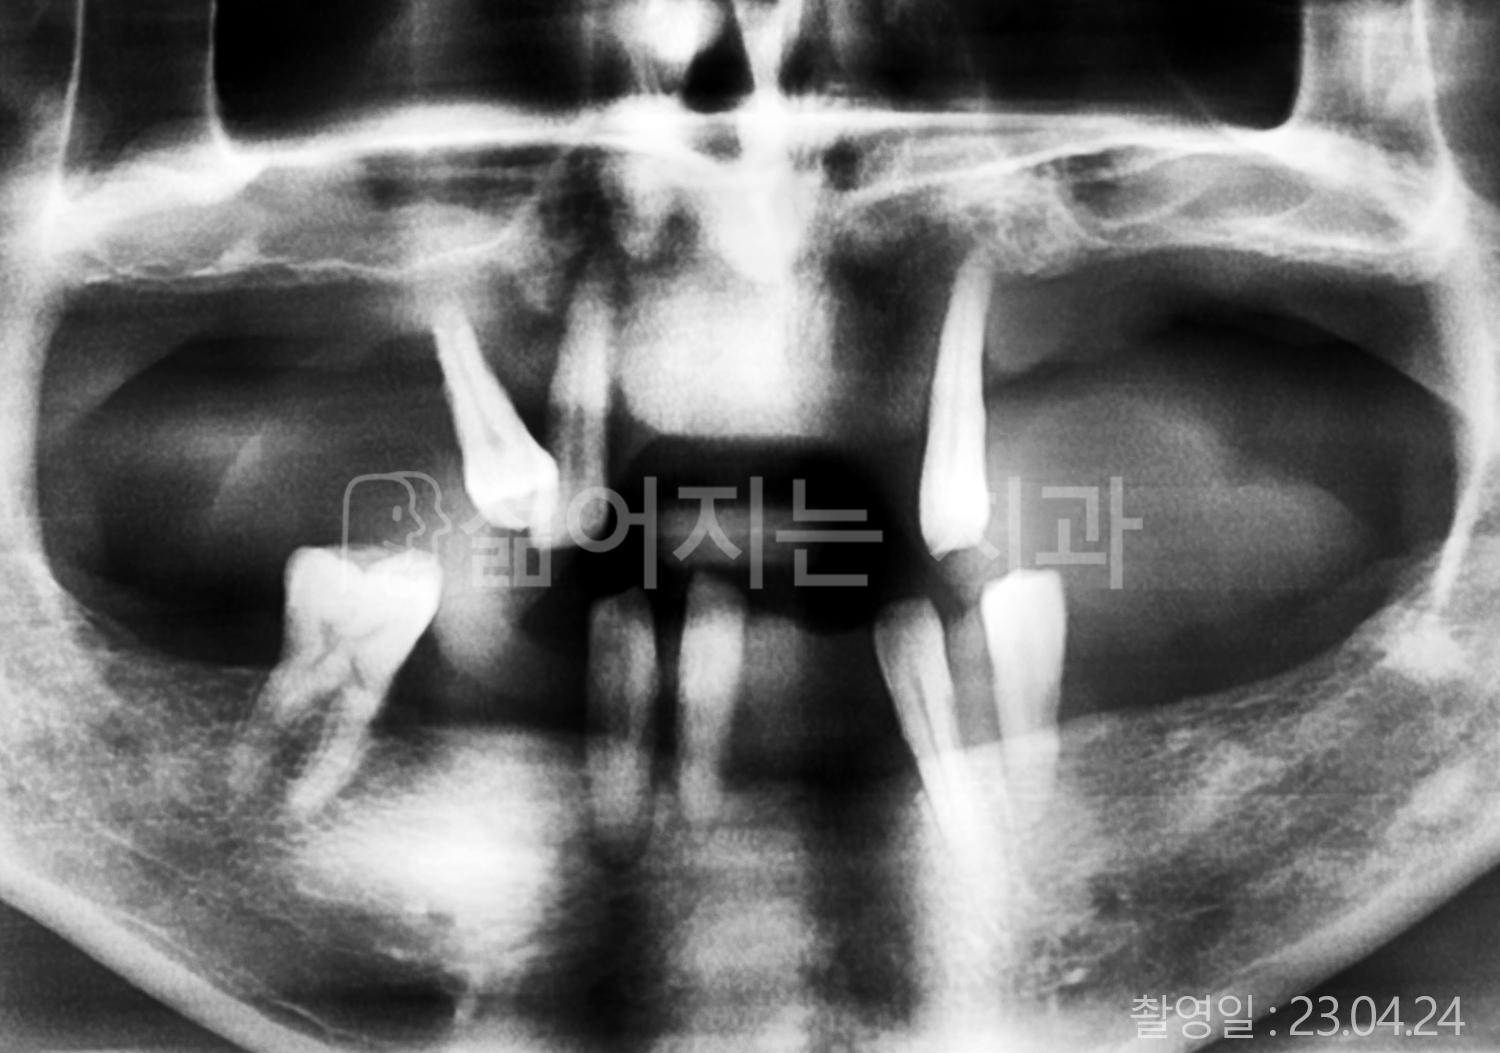

• 40대 전체치아 10개 이상 임플란트

• 70대 당뇨 전체치아 10개 이상 임플란트

• 60대 전체치아 10개 이상 임플란트

• 60대 고혈압, 당뇨, 고지혈증 전체치아 10개 이상 임플란트

• 50대 전체치아 10개 이상 임플란트

• 70대 고혈압, 당뇨 전체치아 10개 이상 임플란트

• 60대 고혈압 전체치아 10개 이상 임플란트

• 50대 고혈압, 당뇨, 고지혈증 전체치아 10개 이상 임플란트

• 60대 고혈압, 고지혈증 전체치아 10개 이상 임플란트